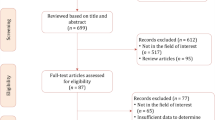

The complete literature search process is presented in Fig. 1. In brief, the initial search identified 260 potentially eligible citations. After removing duplicates, 206 records were screened by the reviewers. After the titles and abstracts evaluation, 192 citations were discharged because they were judged to be non-relevant or non-pertinent. Thus, 14 full-text articles were blindly assessed by each investigator for eligibility. After revision, 2 articles were excluded leaving 12 articles. Furthermore, after screening the reference lists of the eligible studies, we identified one additional article that had not been initially captured in our initial search, despite the presence of the selected keywords. Finally, 13 items were the basis of the present meta-analysis [14,15,16,17,18,19,20,21,22,23,24,25,26].